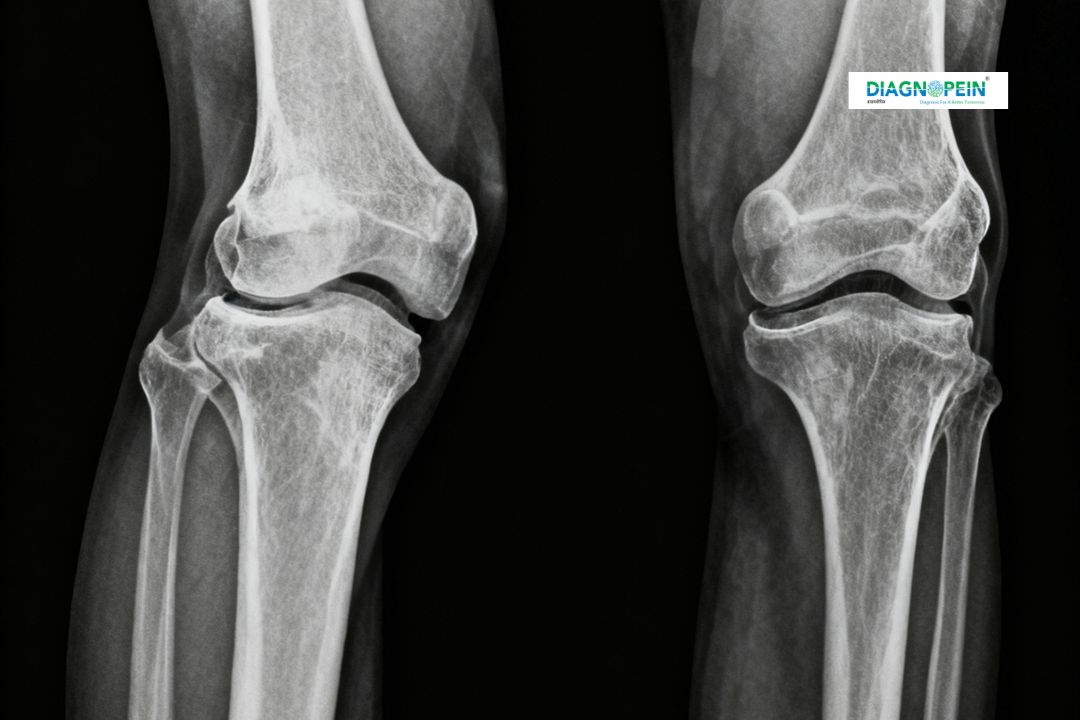

X-Ray Both Knee Standing/Lateral/Skyline 1 View is a specialized diagnostic imaging test used to evaluate the knee joints for bone and joint alignment, degeneration, and injury. This test provides detailed images from different angles—standing, lateral, and skyline views—allowing doctors to assess knee structure and function under natural weight-bearing conditions. At Diagnopein in karad, we use advanced digital X-ray systems that ensure high-quality images with minimal radiation exposure.

X-Ray Both Knee Standing/LAT/Skyline 1 View is important because it reveals how the knee joint behaves under pressure. The standing position helps visualize the joint space and alignment, while the lateral and skyline views give a complete picture of the patella and surrounding bone structures. Performing all three views ensures a comprehensive assessment, aiding in accurate diagnosis and effective treatment planning.

The main parameters assessed during the X-Ray Both Knee Standing/LAT/Skyline 1 View include:

1. Joint space narrowing

2. Bone alignment and deformities

3. Patellar tracking and positioning

4. Bone density and surface smoothness

5. Comparison between both knee joints

6. Signs of wear, tear, or degenerative changes

These parameters help radiologists and orthopedic specialists in Karad determine the severity of the knee condition and plan suitable treatment strategies, such as physiotherapy, medication, or surgery.